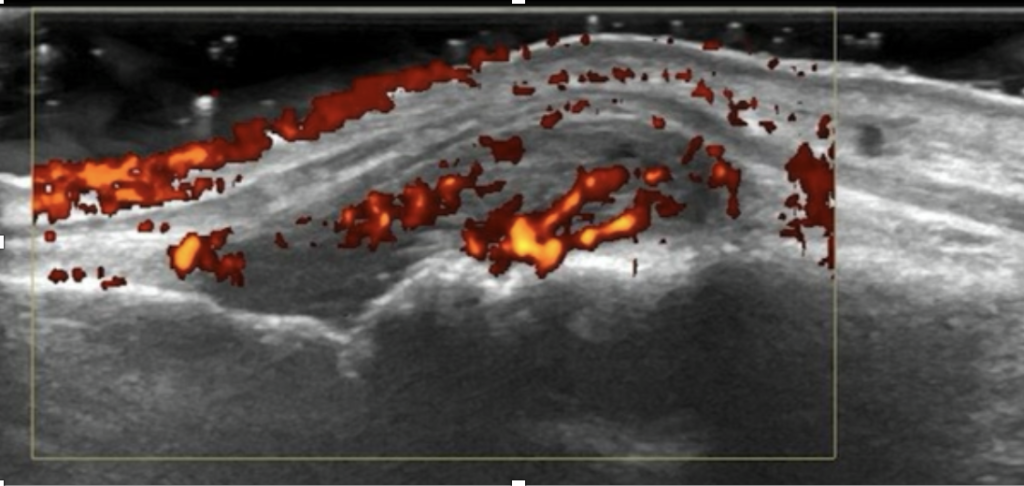

After decades of treating rheumatoid arthritis patients with a “one size fits all” approach, we learned that using the best drug for the right patient at the correct time is possible. When rheumatoid arthritis appears, many different cells migrate to the joints and populate the synovium, a layer of tissue that covers the inside of the joint, causing inflammation, pain, swelling and, ultimately, irreversible damage.

However, the characteristics of the inflamed synovium in rheumatoid arthritis vary significantly between patients, even if their symptoms are the same!